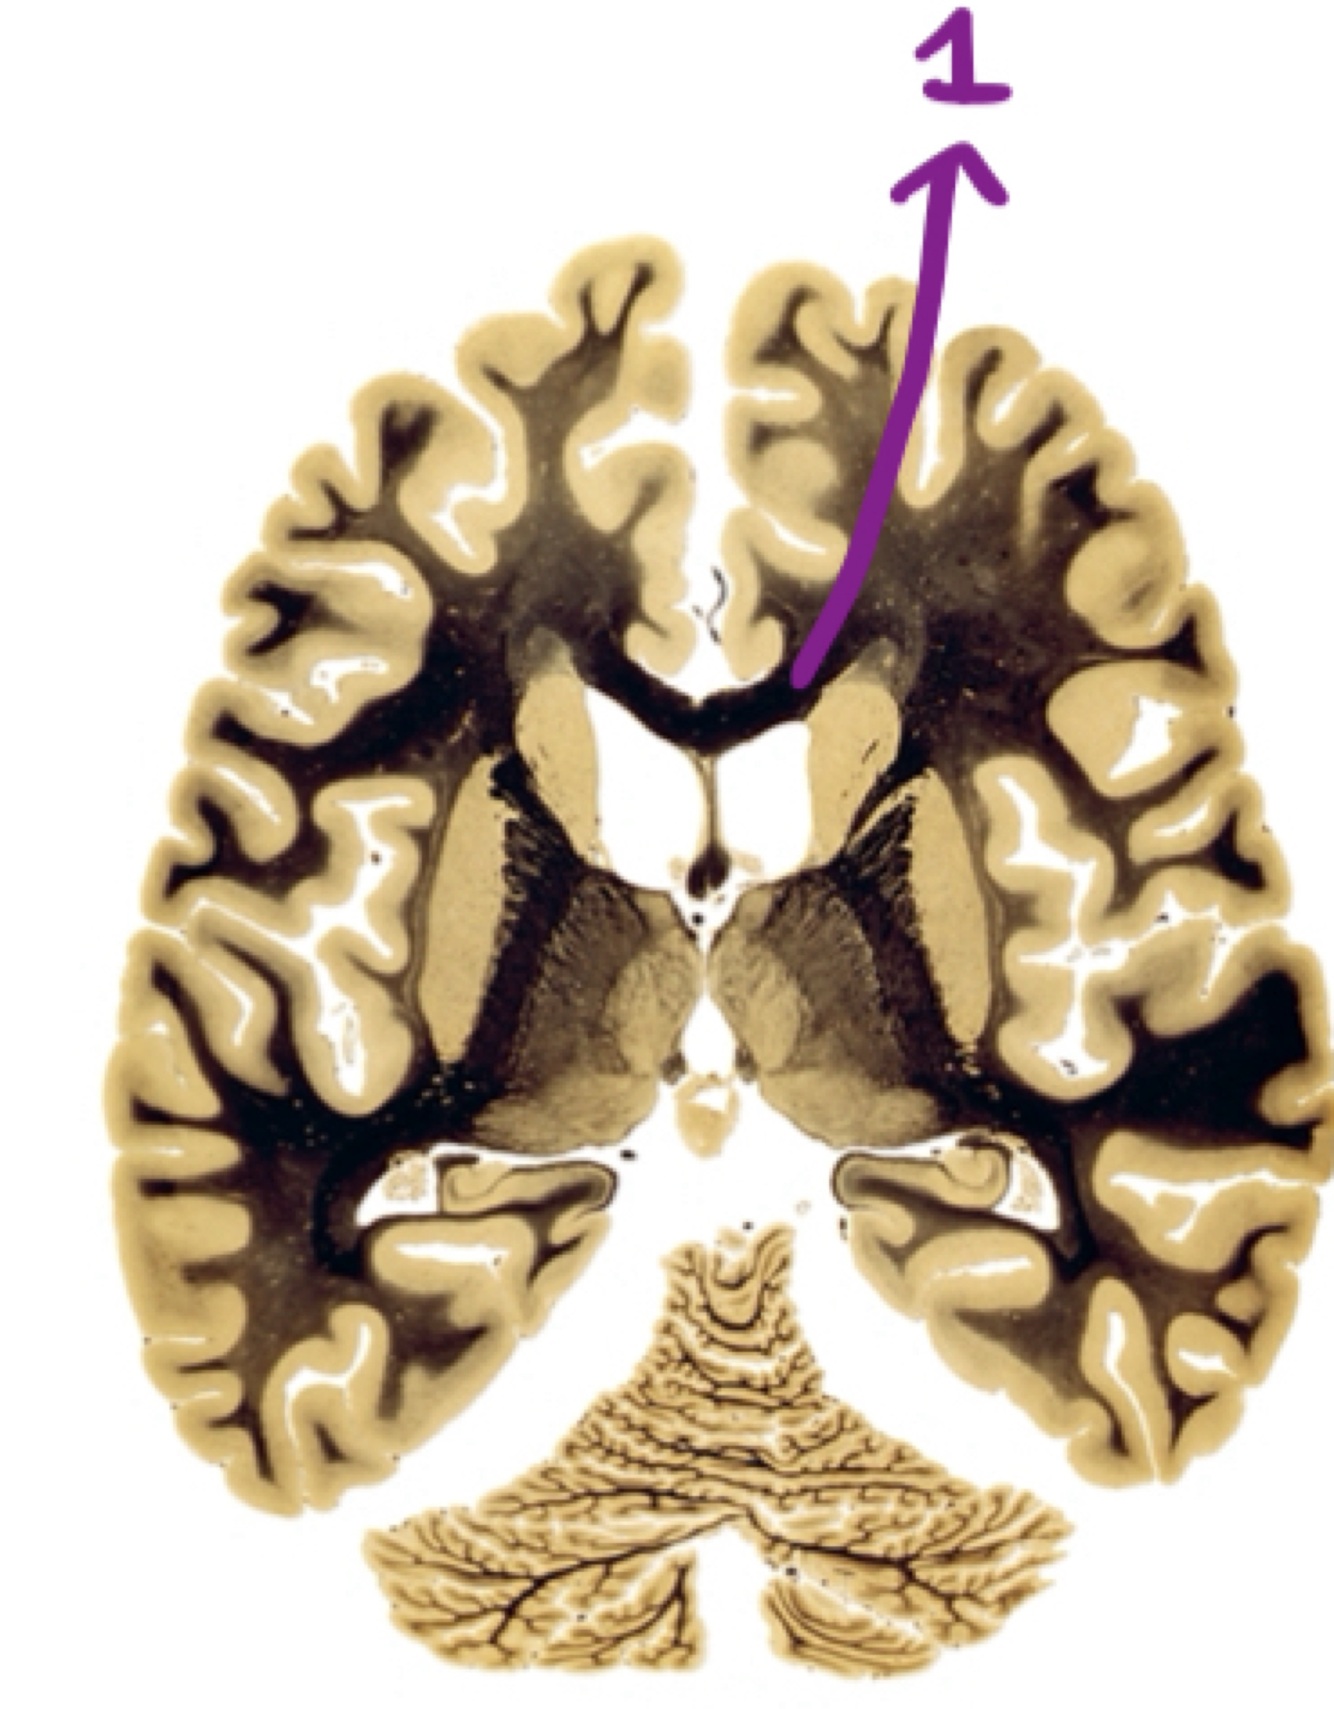

White matter in the cortex

Corpus callosum

The thalamic radiations from the thalamus to the cortex will travel through the…

INTERNAL CAPSULE

Fibers going from the thalamus to the cortex and exiting the cortex pass through…

The internal capsule